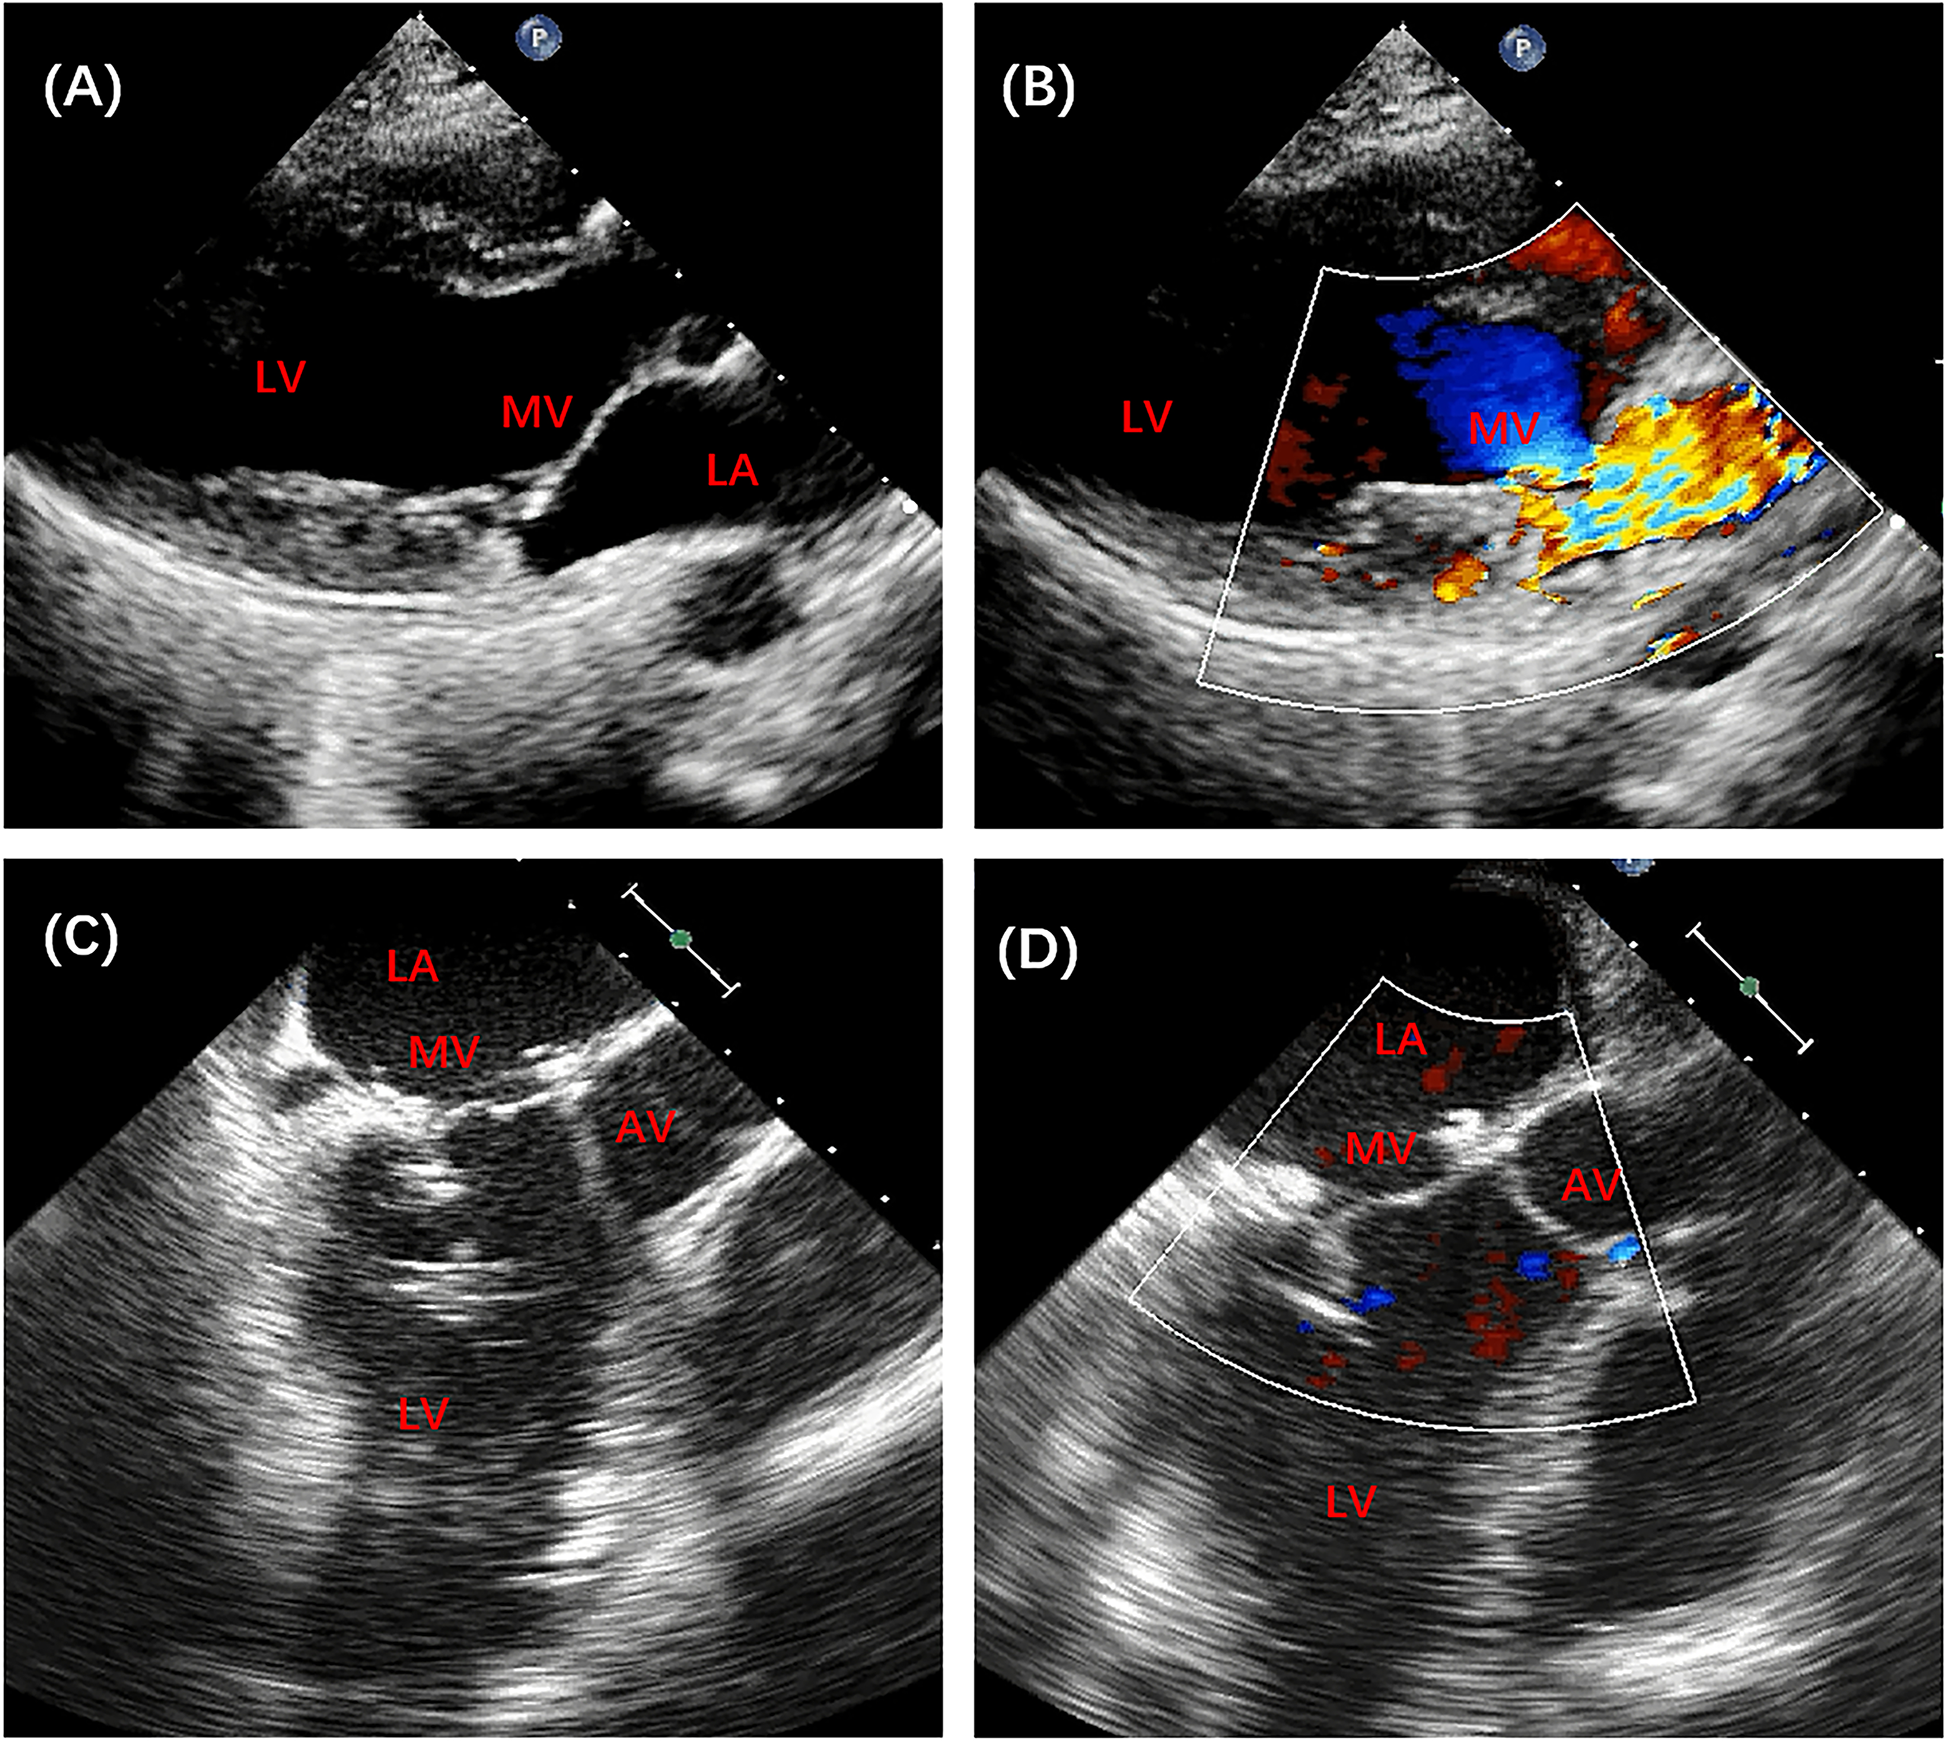

Figure 3

Preoperative and postoperative echocardiography of patient no. 13. (A,B) Preoperative echocardiography revealed severe mitral insufficiency. (C,D) Postoperative echocardiography showed good mitral valve function. AV, aortic valve; MV, mitral valve; LA, left atrium; LV, left ventricle.